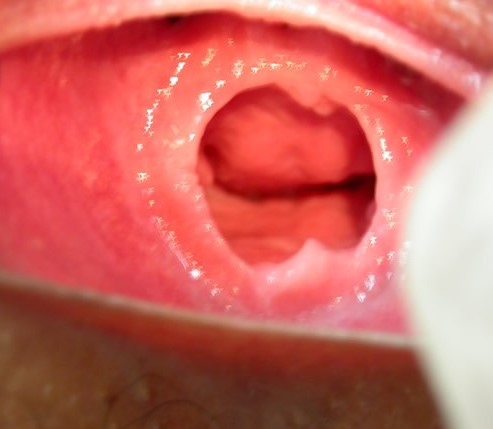

ACTO CONTRANATURA RECIENTE: SE APRECIA UN ORIFICIO ANAL QUE HA PERDIDO SU FORMA ANATOMICA, CON TUMEFACCION Y EQUIMOSIS DE PLIEGUES PERIANALES, PRESENCIA DE HEMATOMA A HORAS XI-XII, FISURA ANAL A HORAS VI.